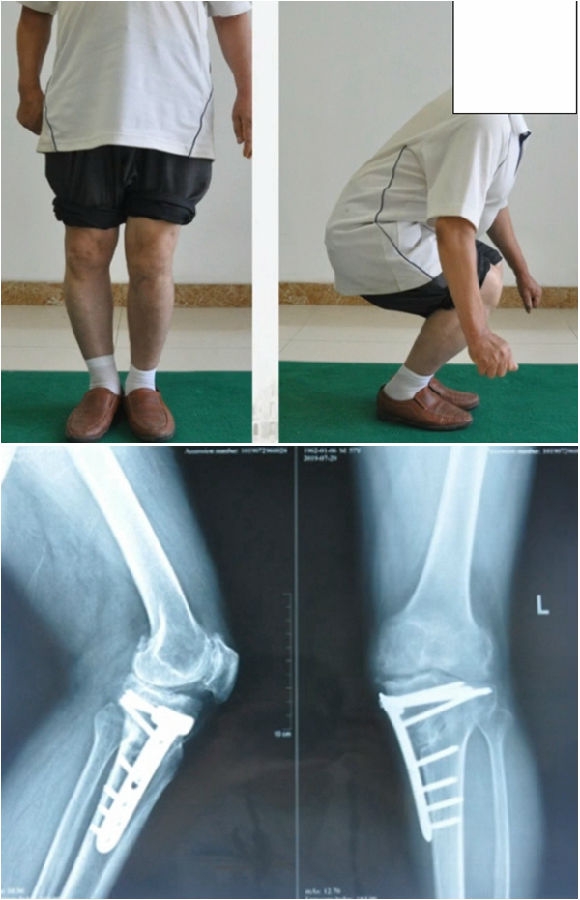

典型病例,男性,57岁,农民,左膝疼痛3年。

术前

术后检查证实达到了术前预期的手术效果,关节线达到了平行,半脱位得到矫正,同时关节线和地面水平。病人行走达到了理想的效果。

术后X线

患者术后4个月截骨愈合,膝关节稳定维持得非常好。

术后4个月

术后9个月完全恢复功能状态。

术后9个月